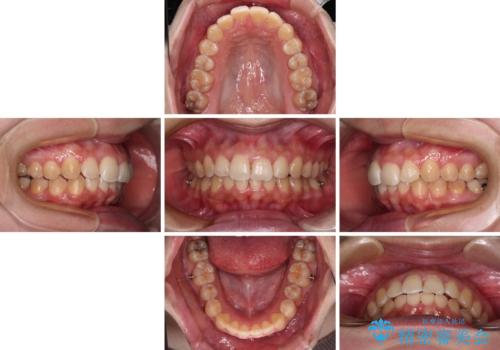

前歯のデコボコをインビザライン矯正で綺麗に改善

- 上下前歯のデコボコを気にして来院された患者様です。

全体的に叢生は軽度であったため、インビザラインにて矯正治療を行うこととしました。

舌の突出癖改善がうまくいかず、途中で舌小帯の切除を行いました。

気になる段差を納得いくまで改善させたため、治療期間は長くなりましたが、綺麗な仕上がりとなりました。